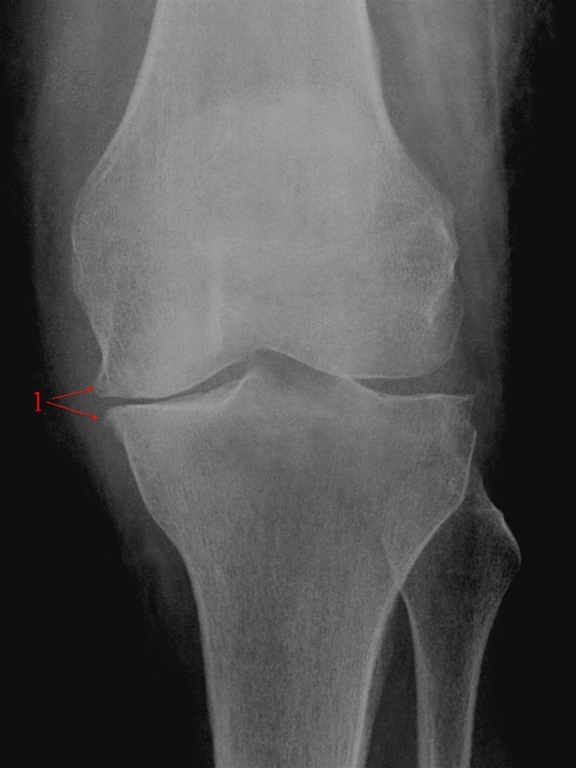

Gonartrose, moderat, front

Moderat artrose medialt i knæleddet. Reduceret bruskhøjde og beskeden randudbygning af knogle (osteofytdannelse) omkring ledfladen (1)